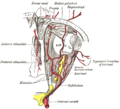

العصب البصريOptic Nerve : هو الزوج الثاني من الأعصاب القحفية الاثني عشر، وهو عصب حسي ينشأ من الخلايا العقدية للشبكية، وتتجمع أليافه في حلمة العصب البصري، ويخرج من كرة العين إلى جوف الحَجاج ثمّ إلى جوف القحف عبر النفق البصري حتى التقاطع البصري وينتهي في النواة الركبية الوحشية.[1]

العصب البصري يتألف من محاور عقد عصبية للشبكية وخلايا Portort. وهو يترك المدار (العين) عبر القناة البصرية ،بشكل postero-medially تجاه chiasm البصرية حيث يوجد partial decussation من الألياف من حقول البصرية للأنف من كلتا العينين. معظم المحور العصبية للعصب البصري تنتهي في lateral geniculate nucleus حيث المعلومات تنتقل إلى القشرة البصرية، في حين أن المحاور العصبية الأخرى تنتهي في الـ pretectal nucleus وتشارك في حركات العين الانعكاسية ومحاور عصبية أخرى تنتهي في suprachiasmatic nucleus وتتدخل في تنظيم دورة النوم واليقظة. ويزيد قطرها حوالي 1.6 ملم من داخل العين، إلى 3.5 ملم في المدار إلى 4.5 ملم داخل فضاء الجمجمة. وأطوال مكونات العصب البصري 24 ملم في المدار، 9 ملم في القناة البصرية و 16 مم في فضاء الجمجمة قبل أن ينضم إلى chiasm البصرية. هناك ،يحدث الـ decussation الجزئي وحوالي 53 ٪ من الألياف تتشابك لتكون الـ optic tracts. معظم هذه الألياف تنتهي في جسم geniculate الأفقي.[2]

التلف في العصب البصري عادة ما يسبب فقدان البصر الدائم والذي قد يكون حاد، فضلا عن pupillary reflex الشاذ، وهو مهم في التشخيص. نوع فقدان البصر سيعتمد على أي من أجزاءالعصب البصري الذي أصيب بأضرار. عموما :

• الضرر قبل chiasm البصرية يؤدي إلى فقدان الرؤية في المجال البصري لنفس الجانب فقط.

• الضرر في chiasm يسبب فقدان الرؤية أفقيا في كل المجالات البصرية (hemianopia bitemporal). وقد يحدث في أورام الغدة النخامية.

• الضرر بعد chiasm يسبب فقدان البصر على جانب واحد ولكنها تؤثر على كل مجالات بصرية : المجال البصري المتضررة يقع على الجانب المقابل من الآفة.